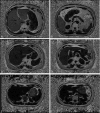

The aim of the study is to investigate if the fat content of the liver and pancreas may indicate impaired glucose tolerance (IGT) or type 2 diabetes mellitus (T2DM). A total of 83 subjects (34 men; aged 46.5 ± 13.5 years) were characterized as T2DM, IGT, or normal glucose tolerant (NGT). NGT individuals were stratified as <40 or ≥40 years. Standard laboratory tests were conducted for insulin resistance and β-cell dysfunction. The magnetic resonance imaging Dixon technique was used to determine fat distribution in the liver and pancreas. Correlations among liver and pancreatic fat volume fractions (LFVFs and PFVFs, respectively) and laboratory parameters were analyzed. Among the groups, fat distribution was consistent throughout sections of the liver and pancreas, and LFVFs closely correlated with PFVFs. LFVFs correlated more closely than PFVFs with insulin resistance and β-cell function. Both the LFVFs and PFVFs were the highest in the T2DM patients, less in the IGT, and least in the NGT; all differences were significant. The PFVFs of the NGT subjects ≥40 years were significantly higher than that of those <40 years. The fat content of the liver and pancreas, particularly the liver, may be a biomarker for IGT and T2DM.